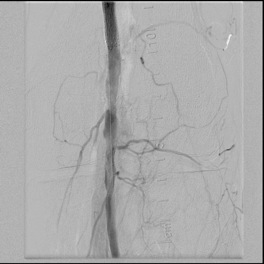

When conduit is limited, or PTFE or cadaver vein is being considered, in the setting of occluded SFA stents, I have found that it is possible and perhaps preferable to attempt removal of these stents using remote endarterectomy.

The CTA, particularly with 3D reconstruction, is helpful in planning these cases.

The additional material needed is fluoroscopy and endovascular skills. Directing a subintimal Glidewire helps free the stent and aid passage of the Moll ring dissector.

Adding cold saline seems to help shrink the stents. A plaque free distal end point allow the stents to be removed with a gentle tug.

I put these patients on coumadin anticoagulation. Surveillance is needed for recurrent stenoses -typically these occur randomly as focal TASC A stenoses, and likely represent remnant medial tissues that have caused intimal hyperplasia. This may be particularly amenable to treatment with drug eluting balloons. Failure as thrombosis typically is limited to the treated vessel without the embolism seen when PTFE grafts fail. Failure tends to occur in smokers. Inability to pass the dissector is usually seen in patients with heavy calcification -diabetics, renal failure, and I would avoid attempting remote endarterectomy in these patients. When the dissectors fail to pass, cutting down and directly endarterectomizing the vessel and resuming remote endarterectomy is feasible. The common femoral artery is repaired with a patch. I try to avoid having to place a distal stent and when a tapered end point, as in a successful carotid endarterectomy, is achieved, usually unnecessary.